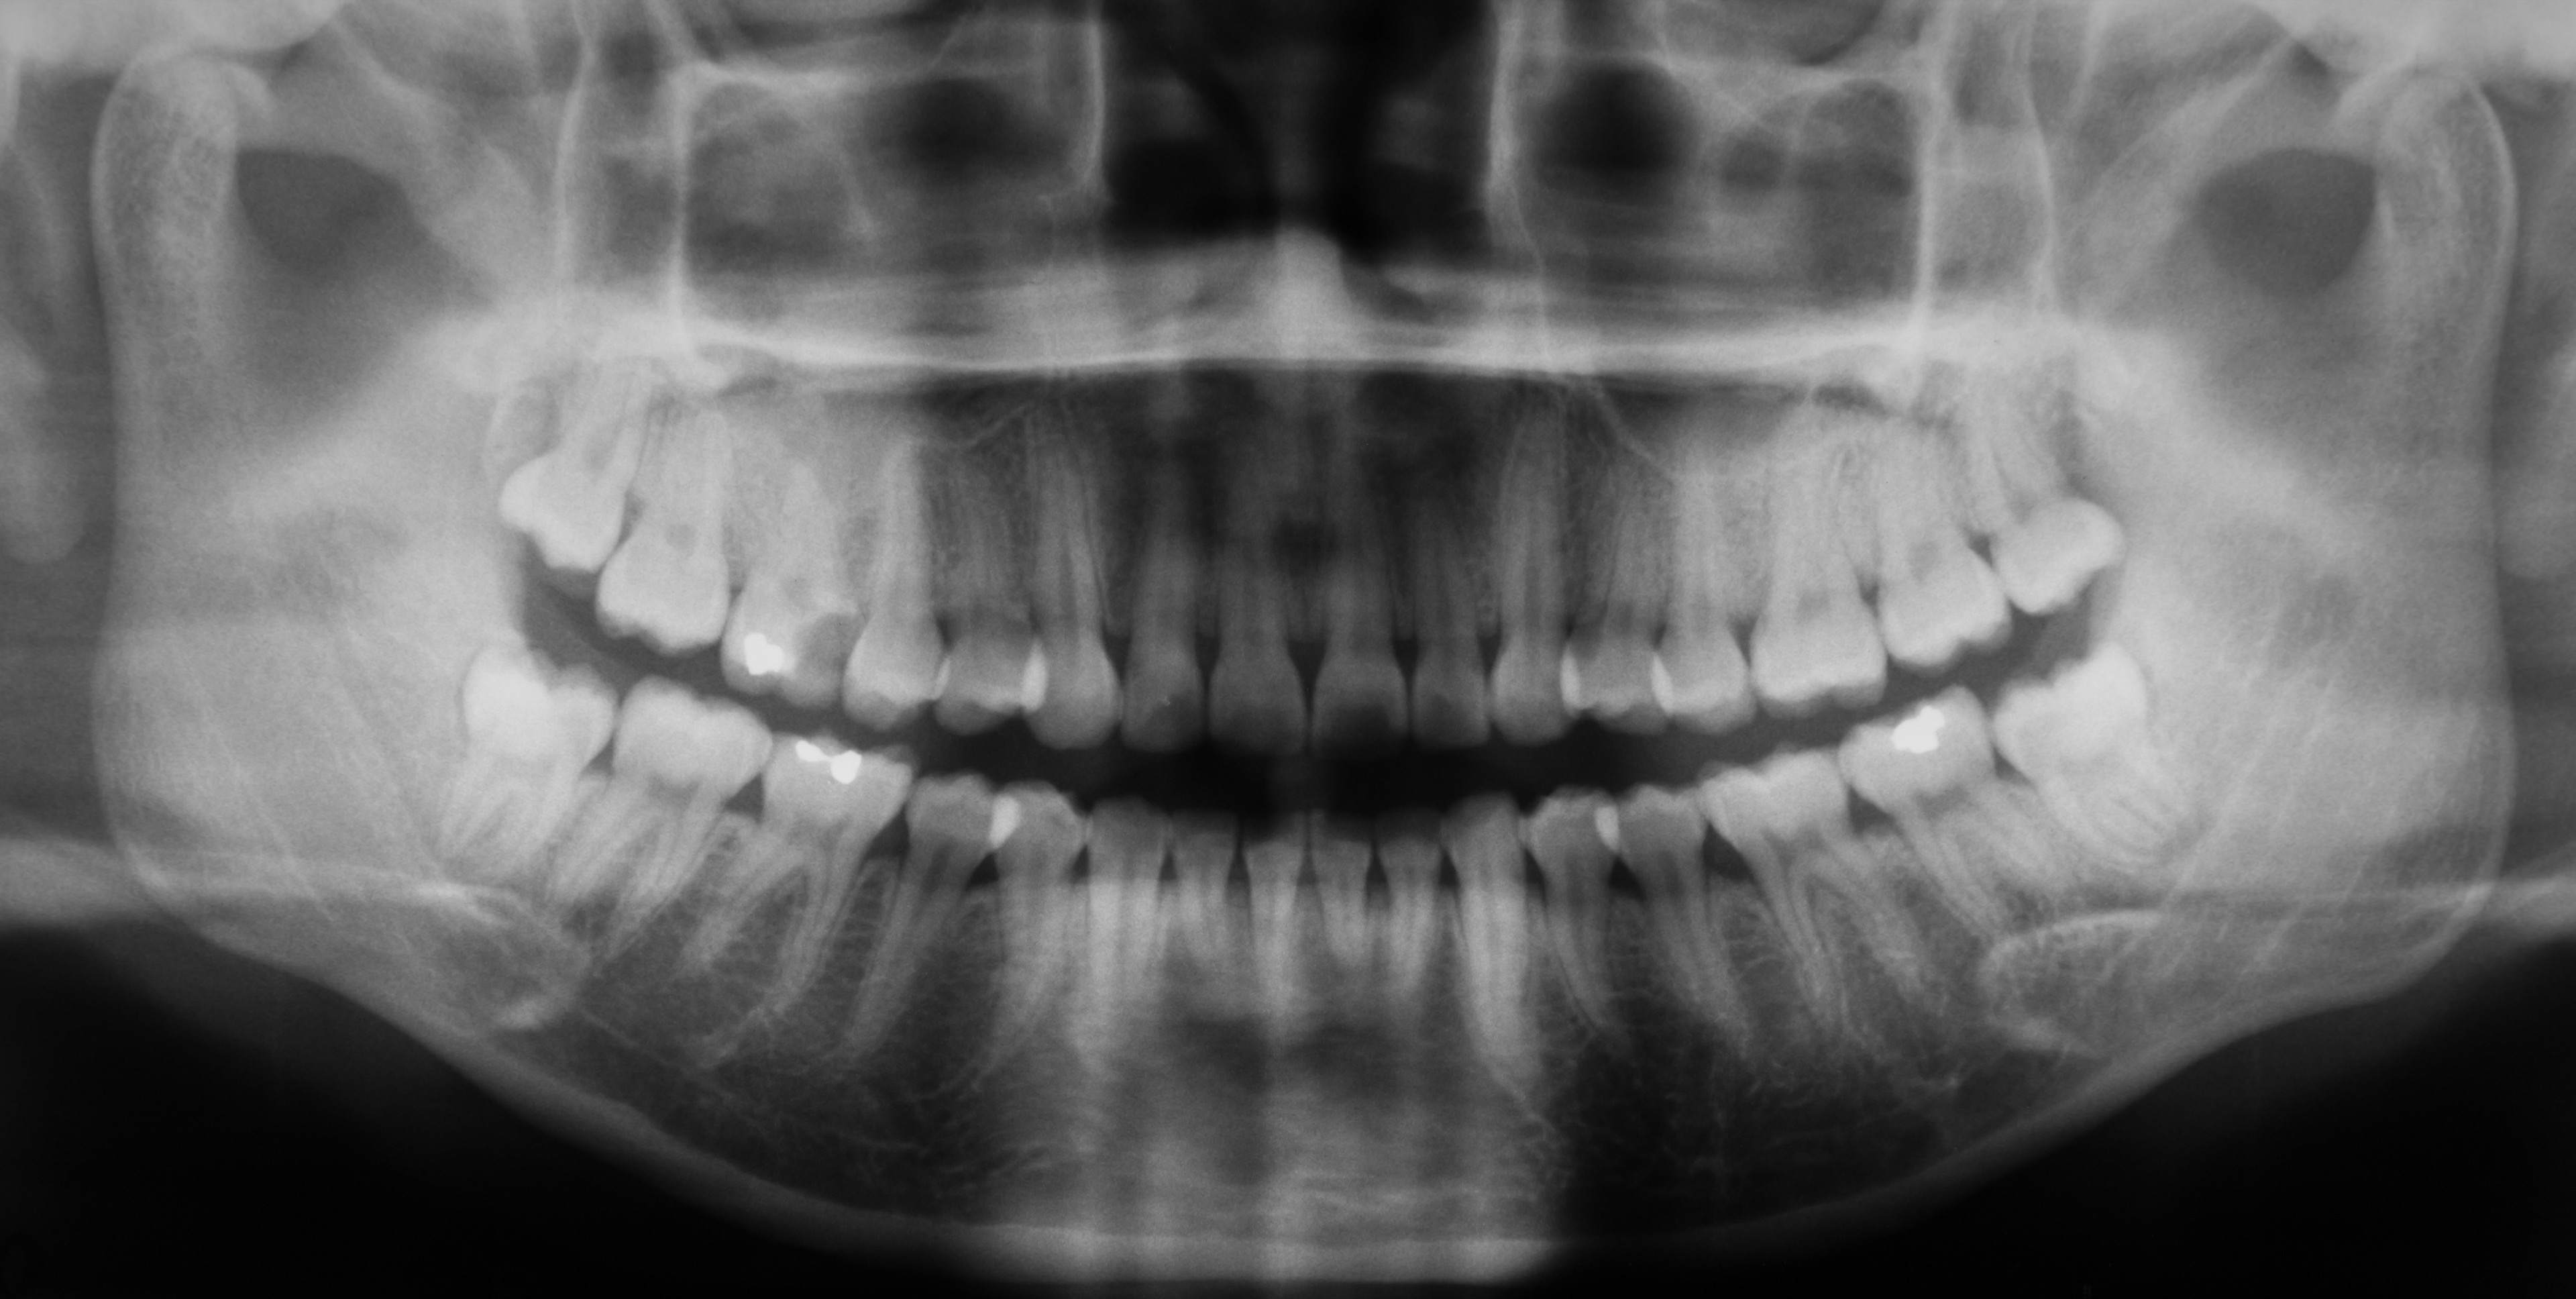

- zdjęcia panoramiczne zębów (całkowite)

- zdjęcia panoramiczne wycinkowe stawów skroniowo_żuchwowych

Zdjęcia pantomograficzne wykonane nowoczesnym aparatem RTG umożliwiają ocenę stawów skroniowo-żuchwowych oraz RTG zatok szczękowych.

RTG pantomograficzne wykonane w klinice stomatologicznej ATJ można poszerzyć RTG stawów skroniowo-żuchwowych, RTG zatok szczękowych czy dokładny rentgen zęba.